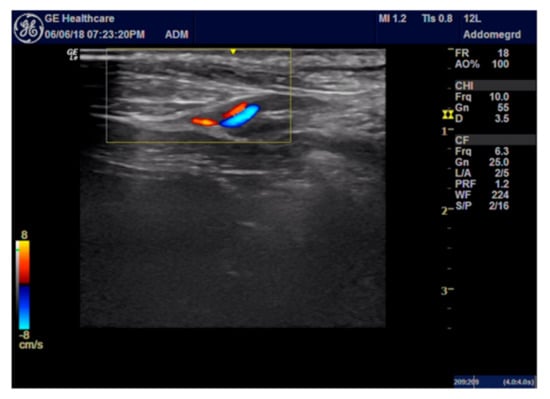

2.4. ROP Group Protocol